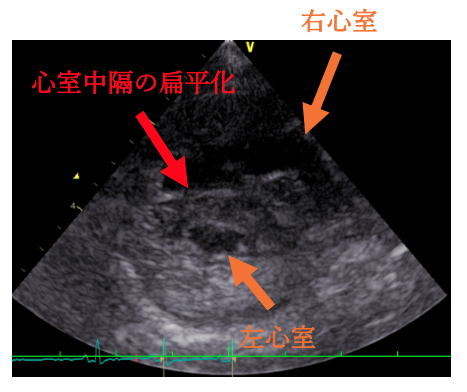

今回の⼼臓超⾳波検査では、 三尖弁からの⾎液の逆流が以前よりも増えていることが確認されました。 また、右⼼室の圧⼒が⾼くなり、左⼼室が押されて細く⾒えるような所⾒や、肺動脈の拡張も認められました。現在、⽇常⽣活で症状はありませんが、⼼臓への負担が以前より増えている状態のため、肺の⾎管を広げて⼼臓の負担を軽減するお薬の内服を始めることになりました。